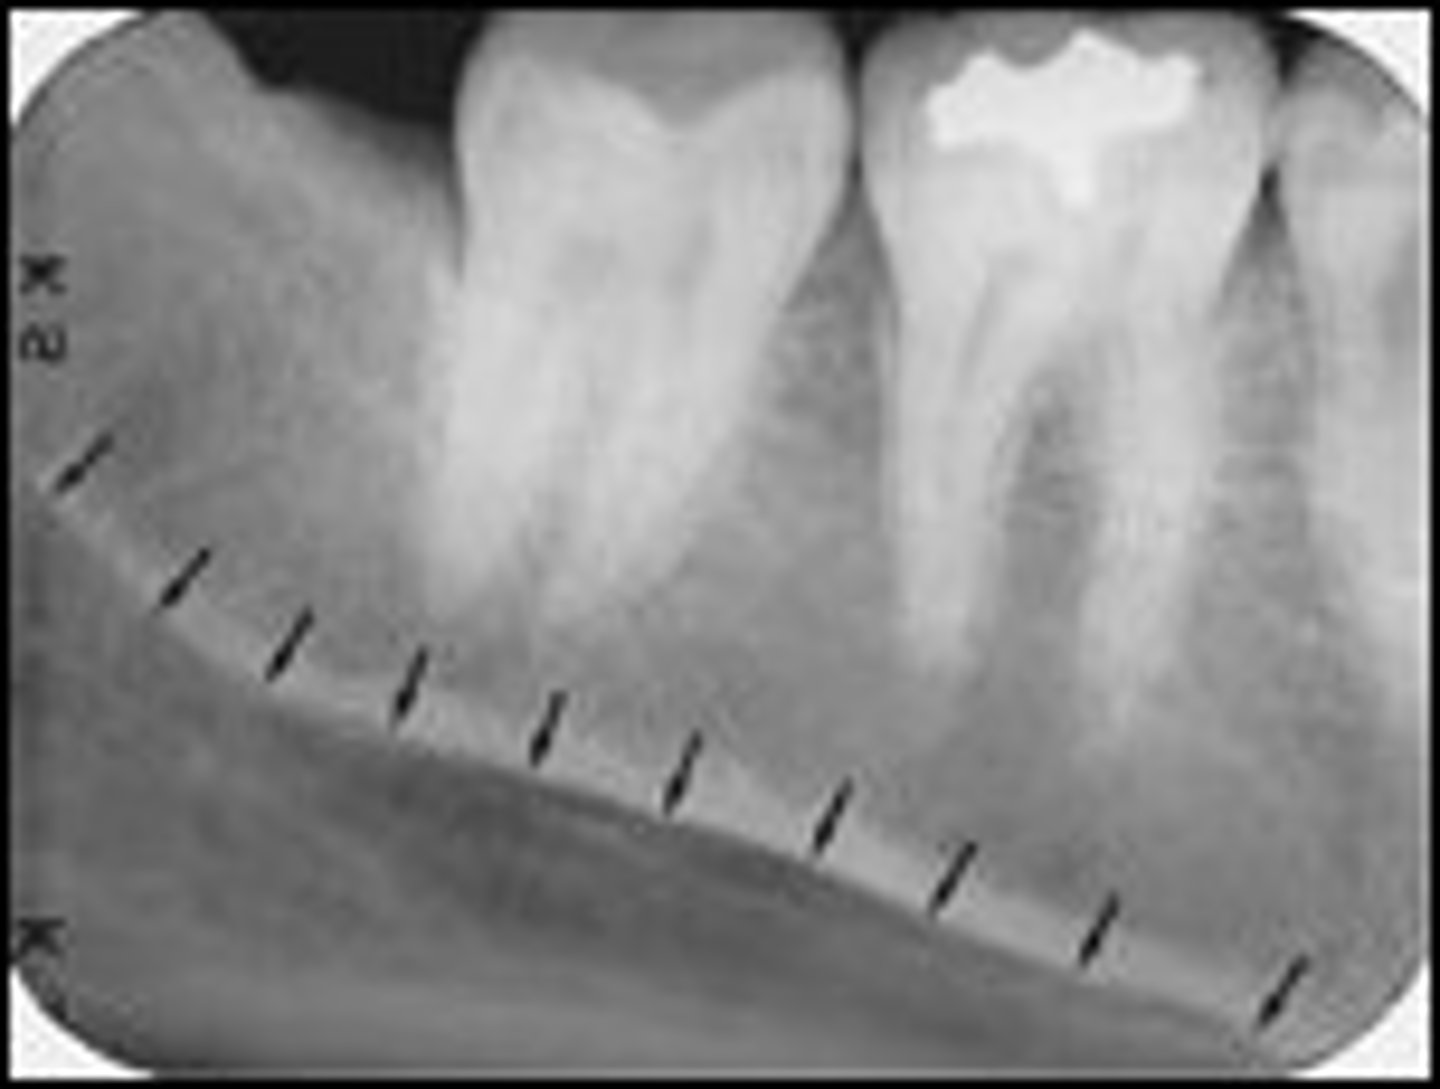

Nutrient canals

What is the radiolucent structure seen here?